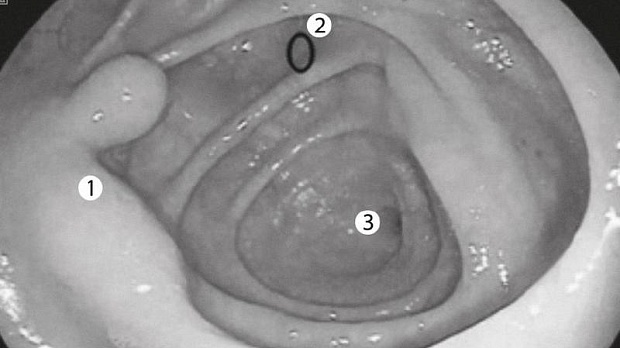

Статьи: Нерешенные аспекты поиска и удаления плоских эпителиальных образований толстой кишки